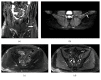

Magnetic resonance neurography is a high-resolution imaging technique that allows evaluating different neurological pathologies in correlation to clinical and the electrophysiological data. The aim of this article is to present a review on the anatomy of the lumbosacral plexus nerves, along with imaging protocols, interpretation pitfalls, and most common pathologies that should be recognized by the radiologist: traumatic, iatrogenic, entrapment, tumoral, infectious, and inflammatory conditions. An extensive series of clinical and imaging cases is presented to illustrate key-points throughout the article.